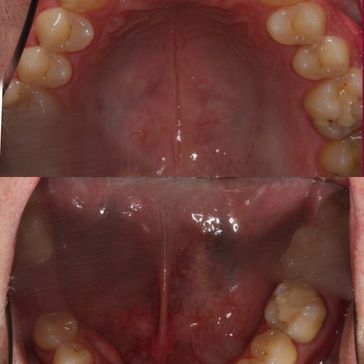

Bei uns können Zahn- sowie Kieferfehlstellungen durch Zahnspangen behandelt werden. Auch Zahnspangen mit weißen Brackets und weißem Draht, die zu einem unauffälligen und dezenteren Erscheinungsbild führen, sind bei uns erhältlich.

Schienen sind oft eine sehr gute Alternative zu festsitzenden Zahnspangen, die wir in Zusammenarbeit mit einem renommierten  Zahntechniker eigens für den Patienten erstellen, um die Zahnfehlstellung zu korrigieren und dem Knirschen entgegenwirken.